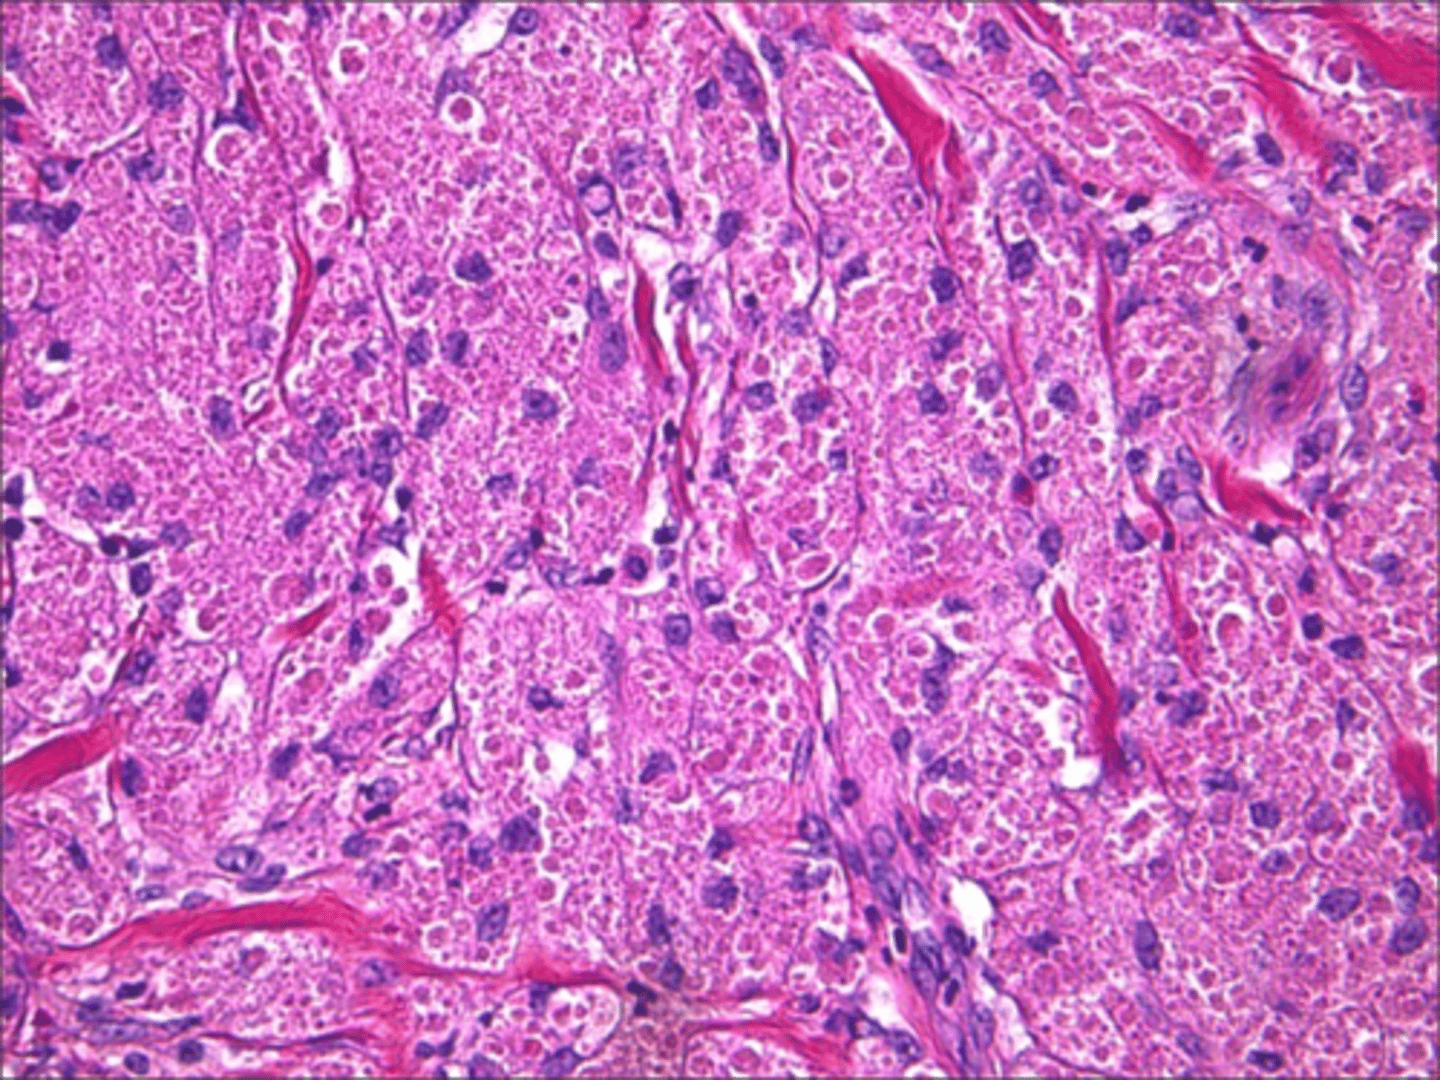

Peripheral Giant Cell Granuloma (PGCG)

patient presents with a purplish, slightly ulcerated nodule on the facial aspect of the maxillary gingiva. Histopathologic features show Multinucleated giant cells with up to several dozen nuclei, hemorrhage and hemosiderin. What do you suspect?

Peripheral Giant Cell Granuloma (PGCG)

Multinucleated giant cells with up to several dozen nuclei, hemorrhage and hemosiderin is associated with what pathology?

local excision down to bone

what is the treatment for Peripheral Giant Cell Granuloma (PGCG)?